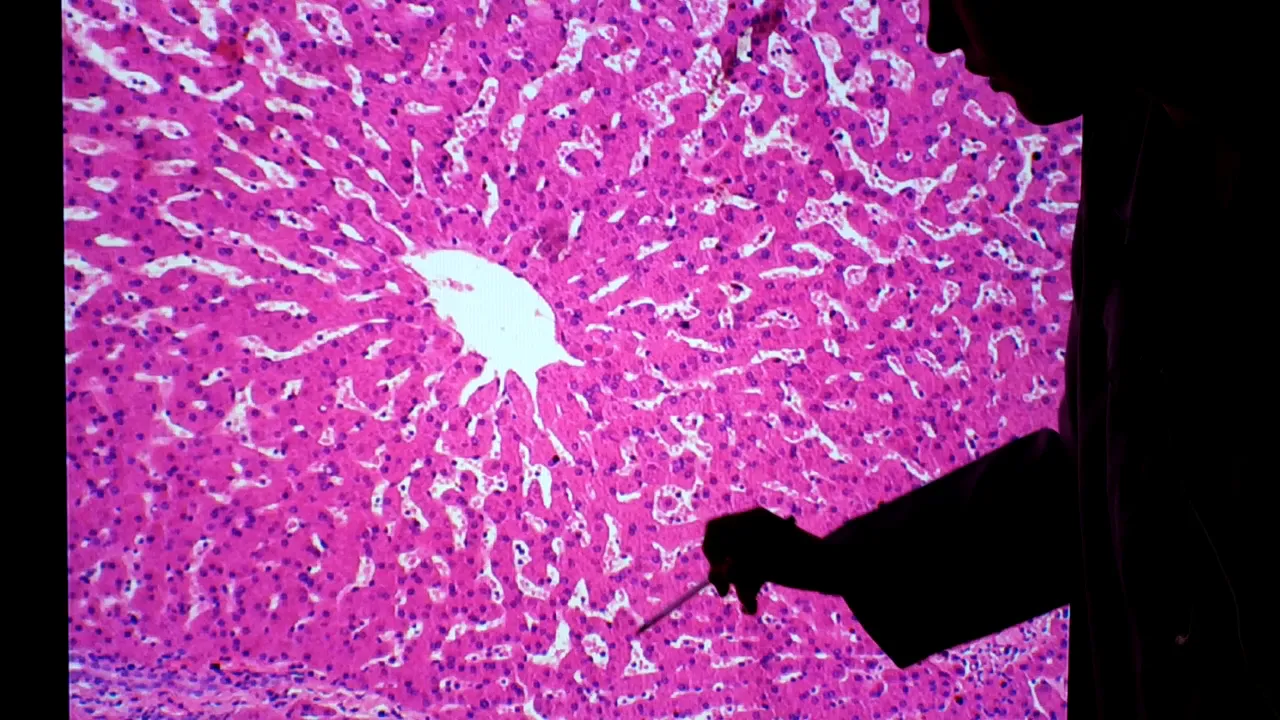

aqui e se tocam vários cordões irregulares ao redor de baleias uma estrutura que são ovos como descrita na virtual anterior aqui a gente também os novos clássicos que claro na holanda não vai ser tão 2012 separação povos quanto ela é uma modelo tecnológico mas dá pra gente ter umas futuras é um desafio é a veia central over sendo lobular do novo álbum clássico essas células rosas são relatórios servem aquela forma vários cordões irregulares geralmente uma ou duas são a sua espessura vários portões foram 2 todos partem aqui do dessa vez central emprestou em celulares sem

um aumento maior em volume do tecido conjuntivo condição fibras colágenas e esse foi um fogo eu vou mexer não provoca um pouco pra ter uma noção geral como este tudo ele é todo formado por molas e só você regulares nem sempre a gente vai conseguir formalizar encontrar a peça teatral e o espaço porta certinho quando aqui pegou um corte mais ou limpo da veia central a proposta de salvação de vela fpv central de assento no popular vão colocar no aumento maior agora pra gente ver com alguns detalhes dessas estamos observando um aumento de 100 vezes

o zoom aqui na veia central bc tomou essa daqui aqui dá pra ver se apresentado ainda o evangelho e agreste em algumas idéias maiores a gente consegue realizar uma efetiva em volta nessa nota da câmera aqui os retoques a nuclear e equivale a uma célula e patácio eles foram cordões regulares ou placas de samba saque do popular de propostas aqui teria outra placa esses passos aqui entre são os capilares seus oitos são capilares sanguíneos é a não ficava bastante dilatados que apresenta pólos na sua parede e com isso permite um contato mas é mais lento

e mais uma opção enquanto aposta para que possa metabolizar as culturas presentes aqui então é que o núcleo de 14 que geralmente é arredondado citoplasma bastante no filho hora de rosa também podemos encontrar algumas células nucleadas aqui próximo ao dos capilares nos olhos e foi provavelmente escala de culpa e uma tropa do fígado que vão fazer para os idosos de partículas maiores que tenham que cheguei o ministro contou que você agora também um aumento maior prestar socorro ainda um aumento de 100 empresas agora uma região mostrando um espaço porta então aqui está o estácio aqui